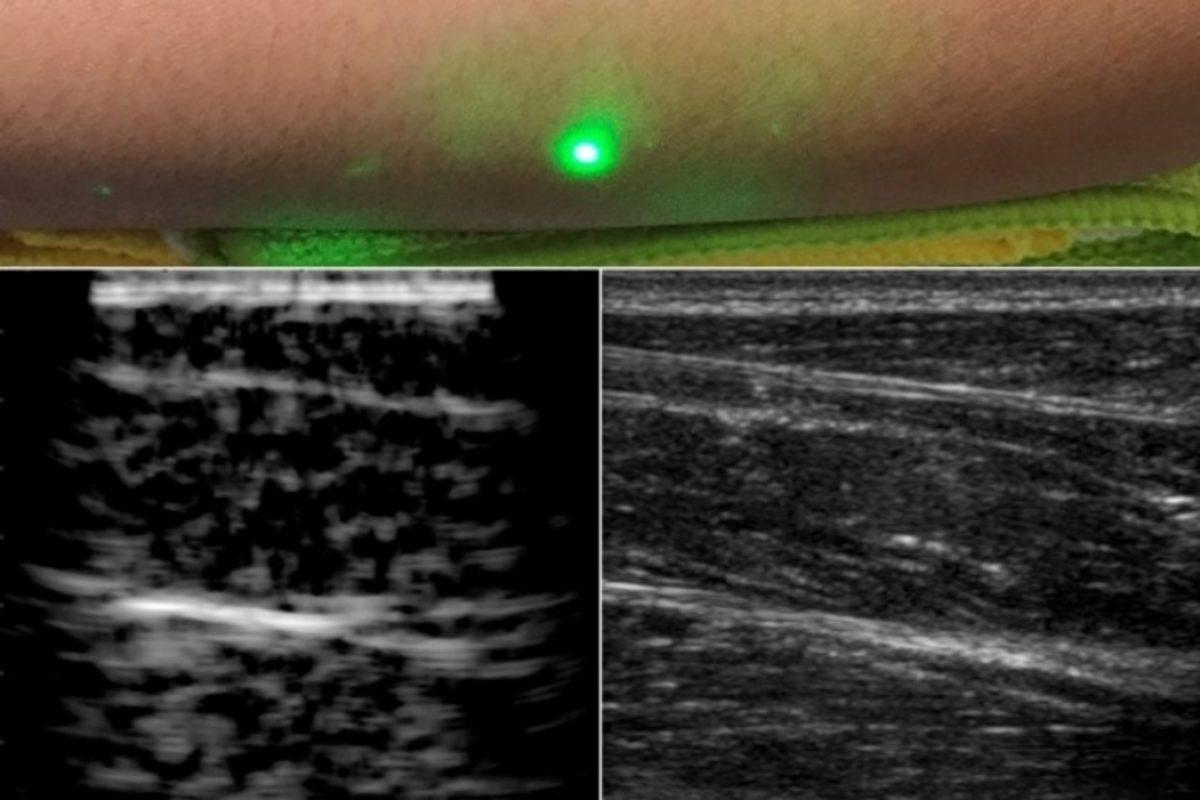

Lazer ultrason tekniği ile elde edilen görüntüler:

MIT araştırmacıları, uyguladıkları yeni yöntem ile 1.550 nanometre dalga boyunda bir lazer ışının insan cildine çarptığında ses dalgaları üretebileceğini keşfetti. Buna göre aynı dalga boyunu takip eden ikinci bir lazer, daha sonra yansıtılan ses dalgalarını tespit edebilir ve geleneksel bir ultrasonunkine benzer bir görüntü oluşturabilir.

Araştırmacılar, bu yeni lazer ultrason tekniğinin, insan derisine benzeyen bir jelatin kalıp üzerindeki ilk testlerde başarılı bir sonuç elde ettiğini söylüyor. Yeni yöntem, şu an için geleneksel ultrason teknoloji kadar net görüntüler sunmuyor; ancak araştırmacılar, geldikleri noktanın bilim ve tıp dünyası için çok önemli bir kilometre taşını simgelediğini ifade ediyor.